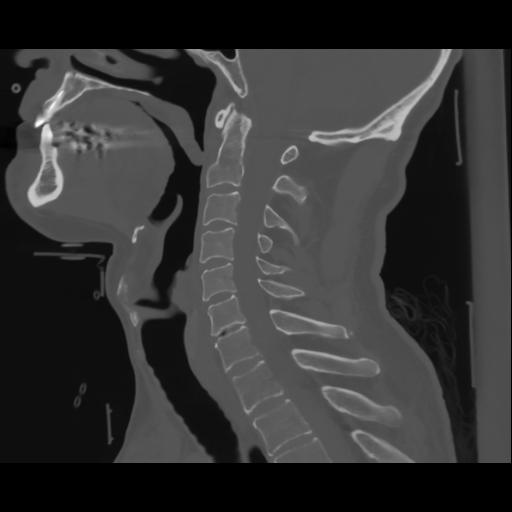

14 P.BLANDAS,,Sagittal,2.000,P.BLANDAS,Sagittal,